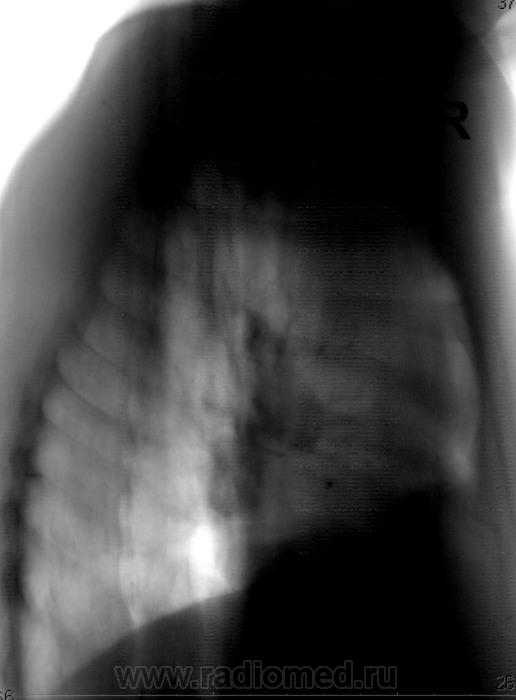

Более контрастные изображения.

Коллеги, а как Вы объясните эту тень? Что-то я на ней зависла. Не ателектаз, не междолевой плеврит. Абдоминомедиастинальная липома?

Тень это жир, по прямому тоже хорошо видно что сердце жирновато

И часто "жир" имеет такие контуры?

А что это еще может быть? Может, на плевре, но по прямому снимку не похоже. Жировая подушка, я считаю, тем более пациент судя по всему не худенький

Как-то сомневаюсь я в абдоминомедиастинальной липоме. Огроменные размеры, фестончатый контур. Подумала ещё о парастернальной диафрагмальной грыже. Валентин Львович, а в архиве что?